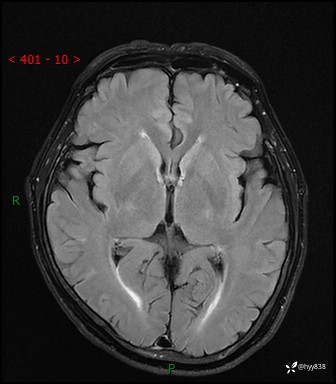

颅脑MRI平扫